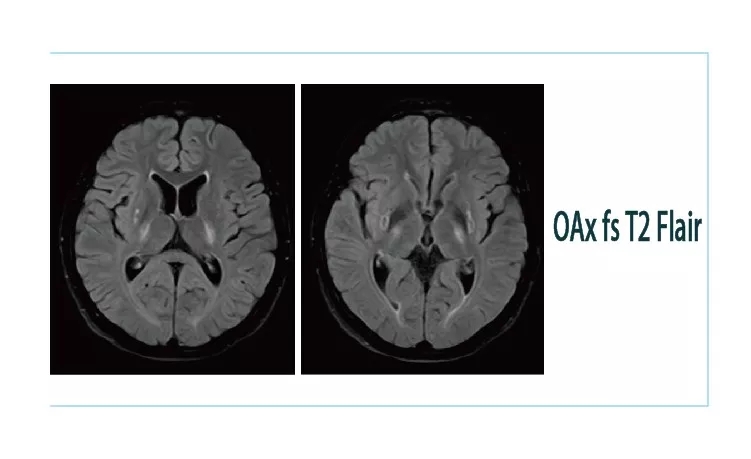

【朗润影像档案】20181130磁共振影像病例结果讨论